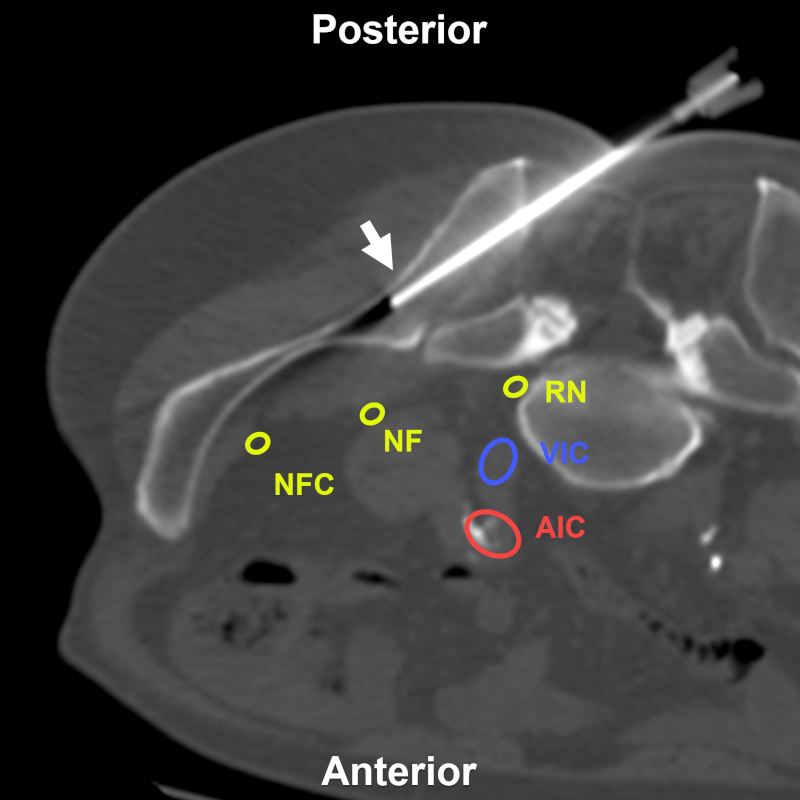

Mujer de 78 años con pérdida de peso significativa y lesión escasamente visible por TC e hipercaptante en la tomografía por emisión de positrones. BP directa transilíaca posterior (flecha) bajo TC. Estructuras a evitar: RN: raíz nerviosa de L5; AIC: arteria ilíaca común; VIC: vena ilíaca común; NF: nervio femoral; NFC: nervio femorocutáneo. Aguja utilizada: Jamshidi 11 G. Diagnóstico final: infiltración secundaria por carcinoma.

Figura 8